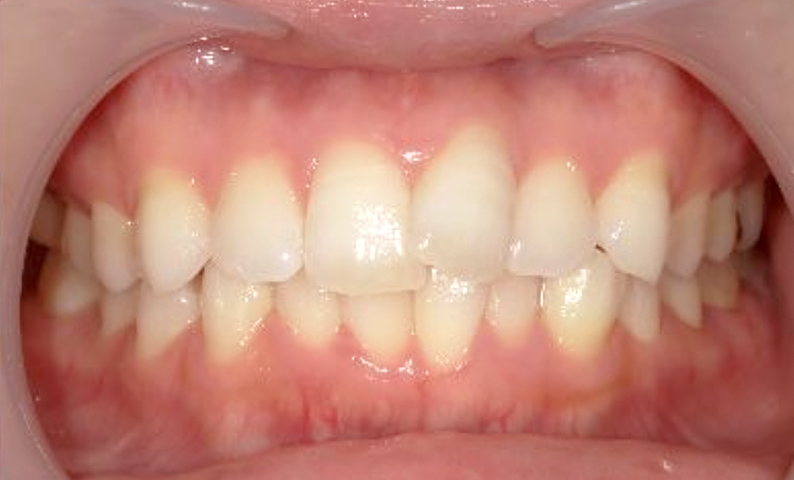

症例_024 上下顎の部分矯正

治療期間:13ヶ月金額:51万円+税女性前歯のガタガタ八重歯

| Before | After |

|---|---|

|